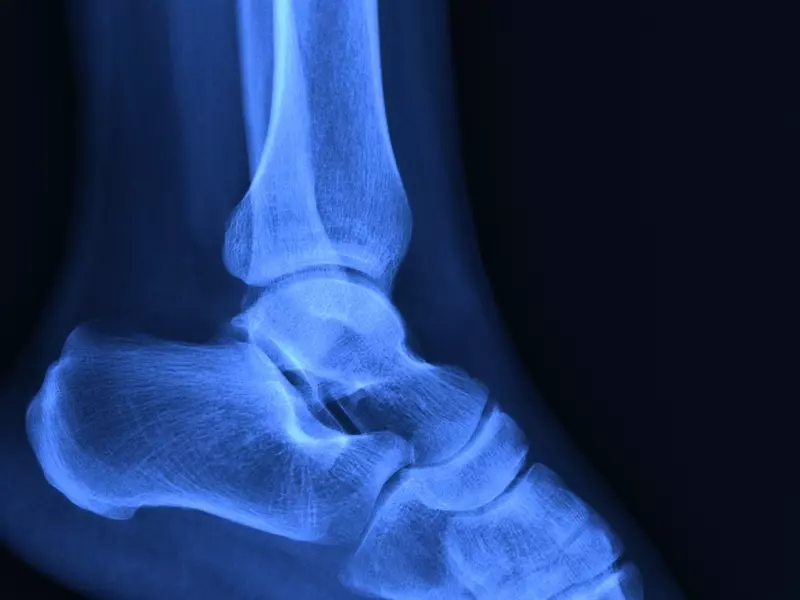

Na szczególną uwagę w obszarze tego stawu zasługuje kość skokowa, z którą w praktyce fizjoterapeutycznej niezbyt często ma się do czynienia. Studiując anatomię stopy, można dostrzec, iż jest to kość o niestandardowej strukturze. Ze względu na jej centralne i wewnętrzne umiejscowienie w całym stawie skokowym nie stanowi ona miejsca przyczepu jakiegokolwiek mięśnia (jedynie licznych więzadeł), tworzy natomiast połączenia z czterema innymi komponentami kostnymi. Z tego powodu większość jej powierzchni przykrywa chrząstka stawowa. Jest to tkanka nieunerwiona oraz nieukrwiona, dodatkowo niepokryta tzw. ochrzęstną, co sprawia, że jej utlenowanie oraz odżywienie są znacznie utrudnione (procesy te zachodzą poprzez dyfuzję tlenu i składników odżywczych z naczyń ochrzęstnej lub mazi stawowej) [2].

Kość skokowa należy do kości krótkich...